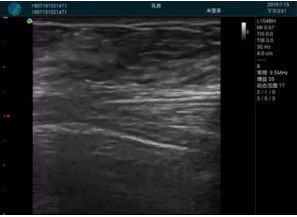

M20查看:囊內(nèi)回聲均勻,邊界清晰,囊壁光滑

M20引導(dǎo)抽吸術(shù)后囊腫消失,原區(qū)域空腔形成,脂肪層與腺體層架構(gòu)發(fā)生改變